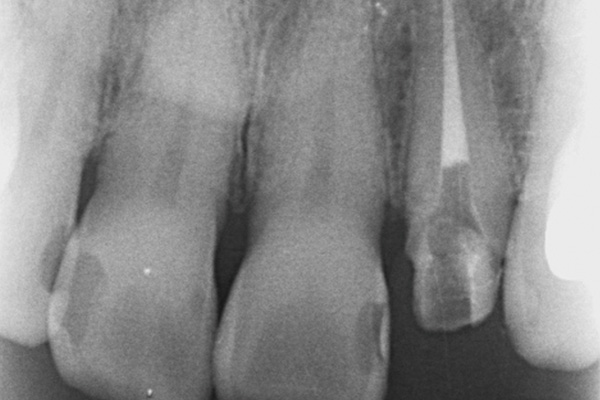

左上前歯の再根管治療

治療概要 精密根管治療 40年前に治療した左上前歯の被せ物が合わなくなったので、根っこの治療からやり直しました。 元々はお薬が不十分だったので、根っこの先まで歯科用顕微鏡を用いて洗浄し、お薬を詰めています。 […]